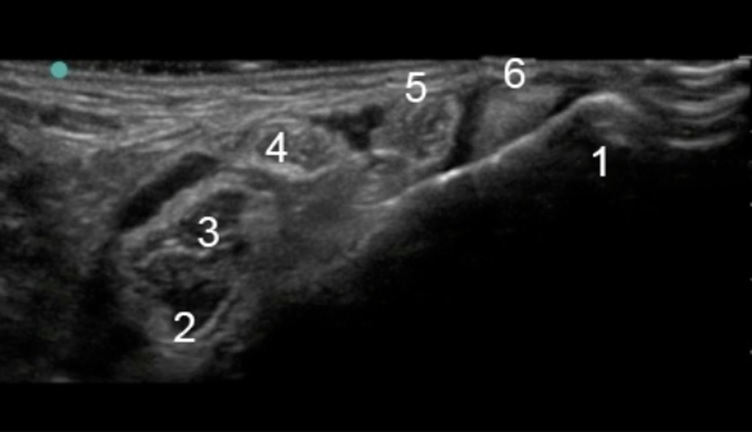

Bild 1: Fuß und Sprunggelenk, medialer Malleolus

1. Medialer Malleolus

2. Flexor hallucis longus

3. Nerve (Nerv)

4. Nerve (Nerv)

5. Flexor digitorum longus

6. Sehne des Tibialis posterior